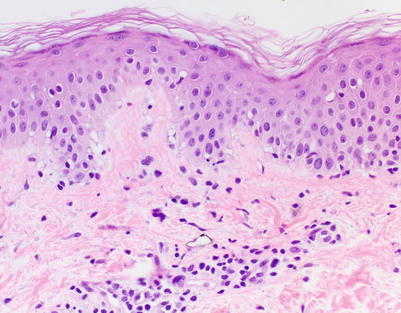

Fig. 5.1

Acute vacuolar interface dermatitis. Basal keratinocyte vacuolization is present, with cytotoxic lymphocytes aligned along the basal layer. Overtly necrotic keratinocytes are absent. These findings correspond to acute graft-versus-host disease (aGVHD) histologic grade I, changes considered insufficiently specific to make a definitive GVHD diagnosis (H&E-stained section, 200× magnification)